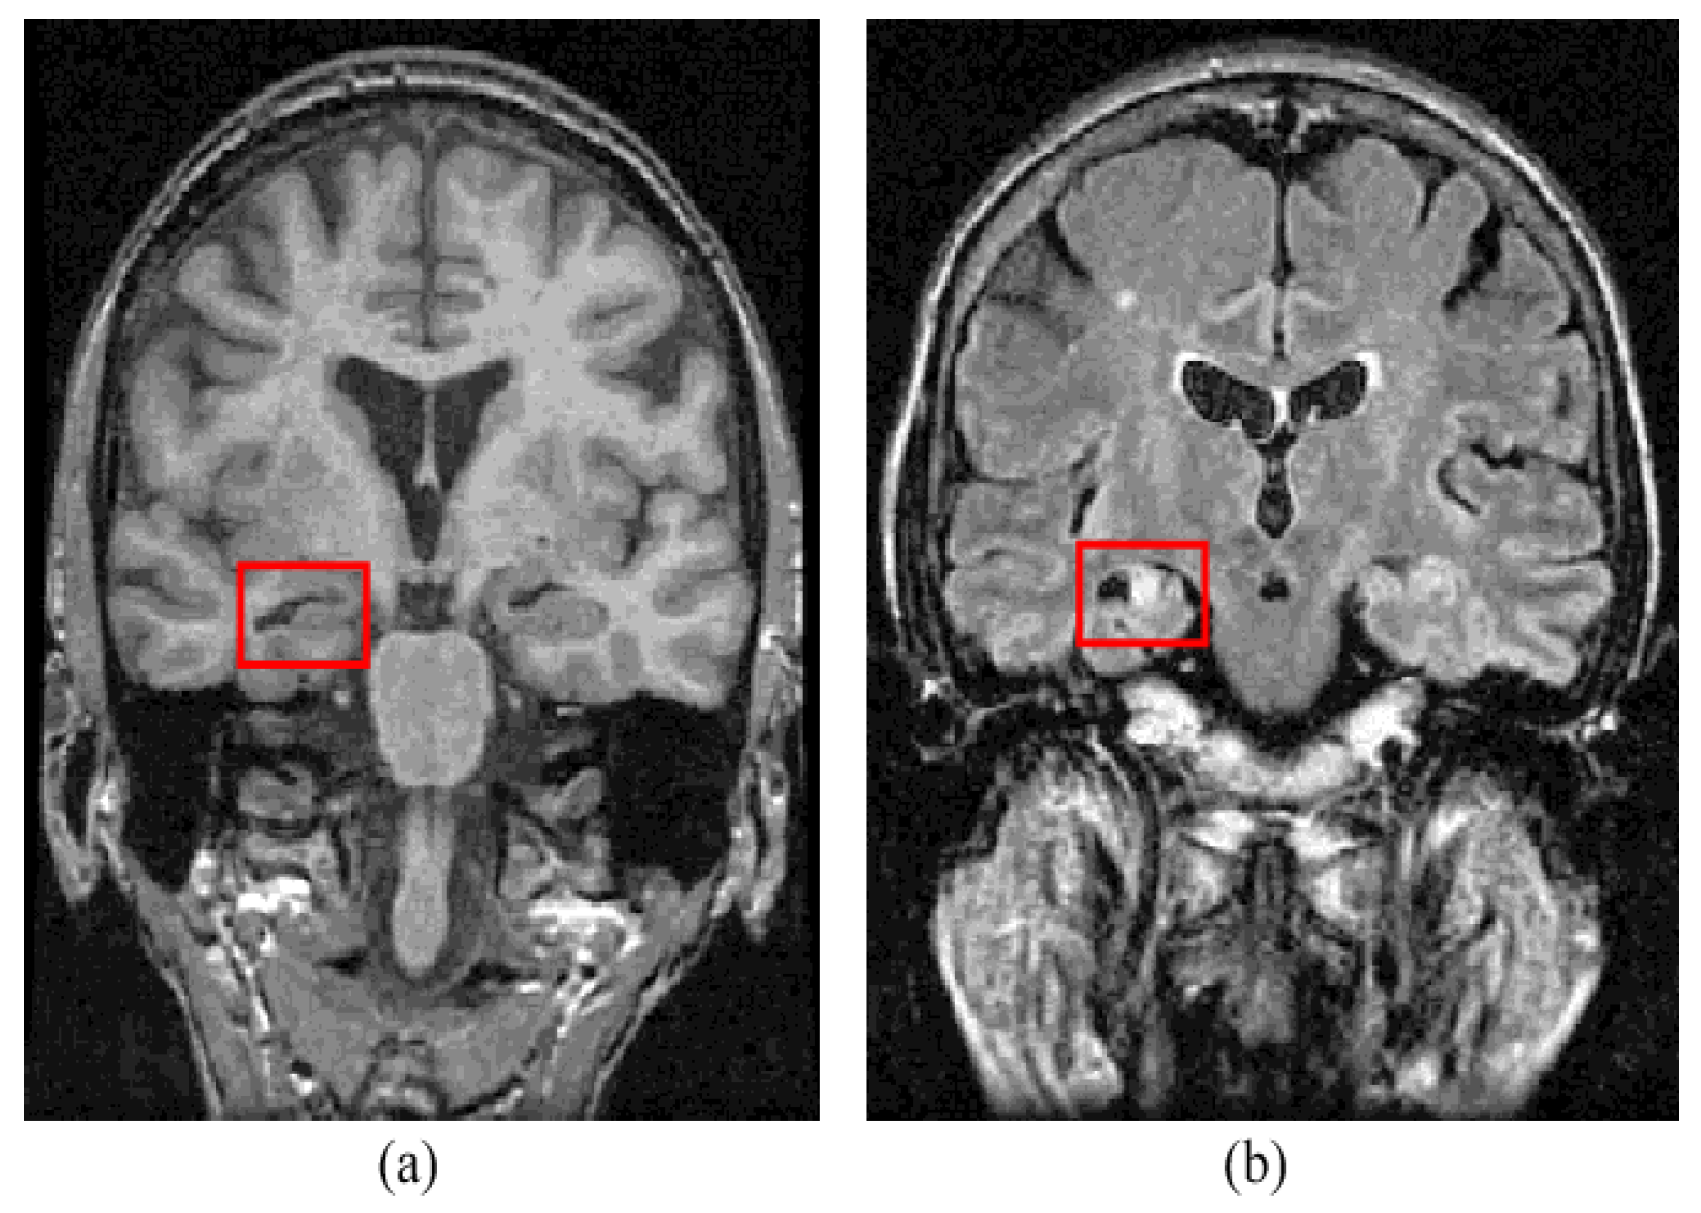

Epilepsy is a neurological disorder. It is characterized by abnormal brain activity. Epileptic patients suffer from unpredictable seizures which cause changes in their behaviour, movement, feelings, and sometimes causes a loss of awareness. The World Health Organization (WHO) estimates that epilepsy affects over 50 million people globally; this large number makes epilepsy the most common neurological disorder. Around three-quarters of epilepsy patients in low- and middle-income countries do not receive the treatment they require, and they and their families face stigma and discrimination in many parts of the world, as per the WHO’s report. Approximately 30% of those patients suffer from refractory seizures [1]. Seizures are considered refractory or drug-resistant when treatment does not succeed in achieving seizure freedom for at least 12 months for any reason [2] or if the treatment fails two or more medicines and a seizure occurs once or more per month over 18 months [3]. During the presurgical workup of drug-resistant epilepsy, specialists seek to determine focal epileptogenic brain lesions to apply resection for those lesions which are predicted to cure epilepsy after resection. Focal cortical dysplasia (FCD) is an epileptogenic lesion that requires surgical intervention for treatment of epilepsy. It is a type of cortical development malformation distinguished by disturbed cortical lamination, balloon cells, dysmorphic neurons, and/or ectopic neurons in the white matter [4,5,6]. FCD type I to FCD type III encompasses a wide range of histological and clinical features [4]; although certain FCDs are easily detectable with traditional neuroimaging, others are more subtle [7]. Neuroradiologists have reported detection rates of FCD type II lesions ranging from 65 to 91 percent [8,9]. Figure 1 shows an example of an FCD lesion. Mesial temporal sclerosis (MTS) is another typical epileptogenic lesion in drug-resistant epilepsy that requires surgical intervention. Figure 2 shows an MTS lesion.

Figure 2.

Mesial temporal sclerosis lesion (a) T1-weighted MRI and (b) FLAIR MRI [11].